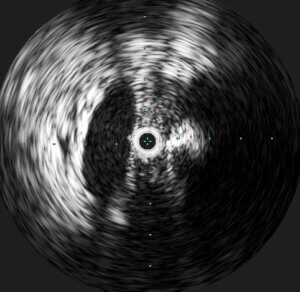

Post-Lysis Image 3

Intravascular ultrasound (IVUS) was performed, which demonstrated the presence of a severe stenosis of the left common iliac vein due to mass effect from the crossing right common iliac artery. This finding is diagnostic of a May-Thurner lesion, which was the underlying anatomic abnormality predisposing this young patient to an extensive DVT.